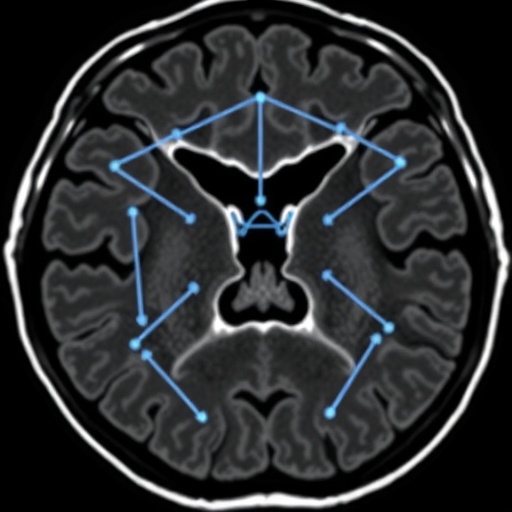

With anterior disc displacement affecting countless individuals, understanding the underlying anatomical changes is crucial. The study employs advanced imaging techniques, specifically axial magnetic resonance imaging (MRI), to assess the angles of the condyle and the lateral pterygoid muscle, providing an innovative approach to visualizing these critical components of the TMJ. Through this detailed imaging, researchers can gather essential quantitative data that may influence future therapeutic techniques and surgical interventions for patients afflicted with ADD.

The researchers’ use of MRI technology is particularly noteworthy. Unlike traditional imaging methods, MRI offers superior soft tissue contrast, allowing for a more nuanced understanding of the TMJ’s components. The study utilized this imaging capability to analyze the angles associated with the condylar and muscle orientations in a cohort of patients diagnosed with ADD. By establishing normative data, the researchers can begin to delineate the boundaries of what constitutes healthy anatomy versus pathological changes that might warrant intervention.